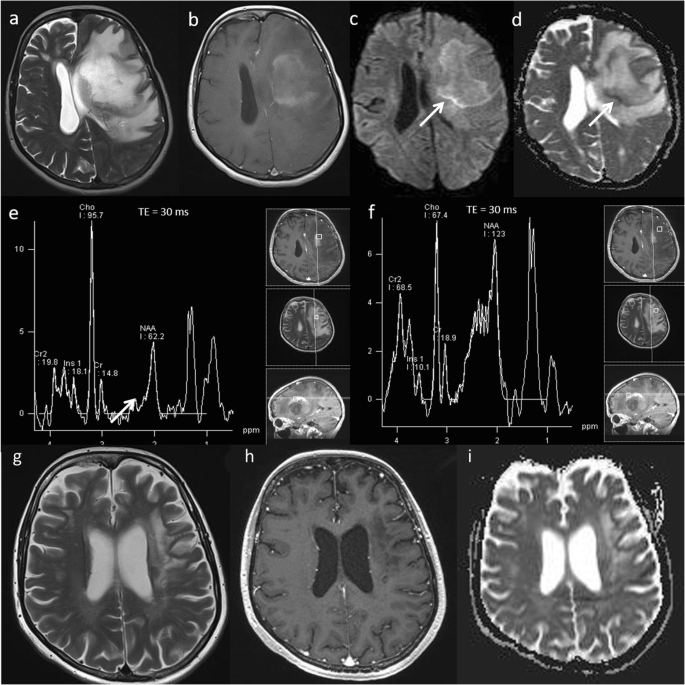

Tumefactive demyelination

Multiple sclerosis is a chronic inflammatory disease of the central nervous system. ‘Tumefactive demyelination’ is the term given when clinical and imaging findings are indistinguishable from those of a neoplastic mass lesion. This is estimated to occur in about 1–2 out of every 1000 cases of multiple sclerosis [49]. Acute tumefactive lesions can have ill-defined borders, mass effect, surrounding oedema, central necrosis and contrast enhancement, which mimic tumour [50]. They usually demonstrate central high ADC, a thin rim of low ADC (representing the active zone of demyelination), generally low rCBV, high Cho/Cr ratio, high glutamate and glutamine (demonstrating inflammatory activity) and presence of lipid and lactate. The metabolic profile from the adjacent perilesional area usually shows a similarly abnormal spectral pattern. MRS should not be read in isolation as it can mimic tumoural spectrum; however, the combination of parameters will lead to the correct diagnosis of tumefactive demyelination. A case of tumefactive demyelination is shown in Fig. 16a–f. The patient avoided biopsy and follow-up imaging shows significant improvement (Fig. 16g–i).

Tumefactive demyelination. Conventional MRI: a, b T2W and post-contrast T1W sequences reveals a large heterogeneous space occupying mass lesion and diffuse pattern of enhancement. Multiparametric MRI: c, d DWI and ADC images show high ADC centrally (> 1000 × 10−6 mm2 s−1) and a thin rim of low ADC reflecting advancing edge of demyelination (arrow). e MRS shows a high Cho/Cr ratio (6.4), near normal NAA/Cr ratio, high glutamate and glutamine (arrow), low mI/Cr ratio and the presence of lipid and lactate at 0.9 ppm and 1.3 ppm respectively. f The metabolic profile from the adjacent perilesional area also shows a similarly abnormal spectral pattern. PWI (not shown) demonstrated a low rCBV except in the anterior-superior component. The striking presence of glutamine and glutamate on MRS, the enhancement pattern and generally low perfusion favour an inflammatory lesion, as opposed to high-grade glioma or lymphoma. The patient made a recovery on methylprednisolone. One-month follow-up imaging: (g) Axial T2W, (h) post-contrast T1W and (i) ADC map shows significant improvement in mass effect, midline shift and overall volume of the lesion